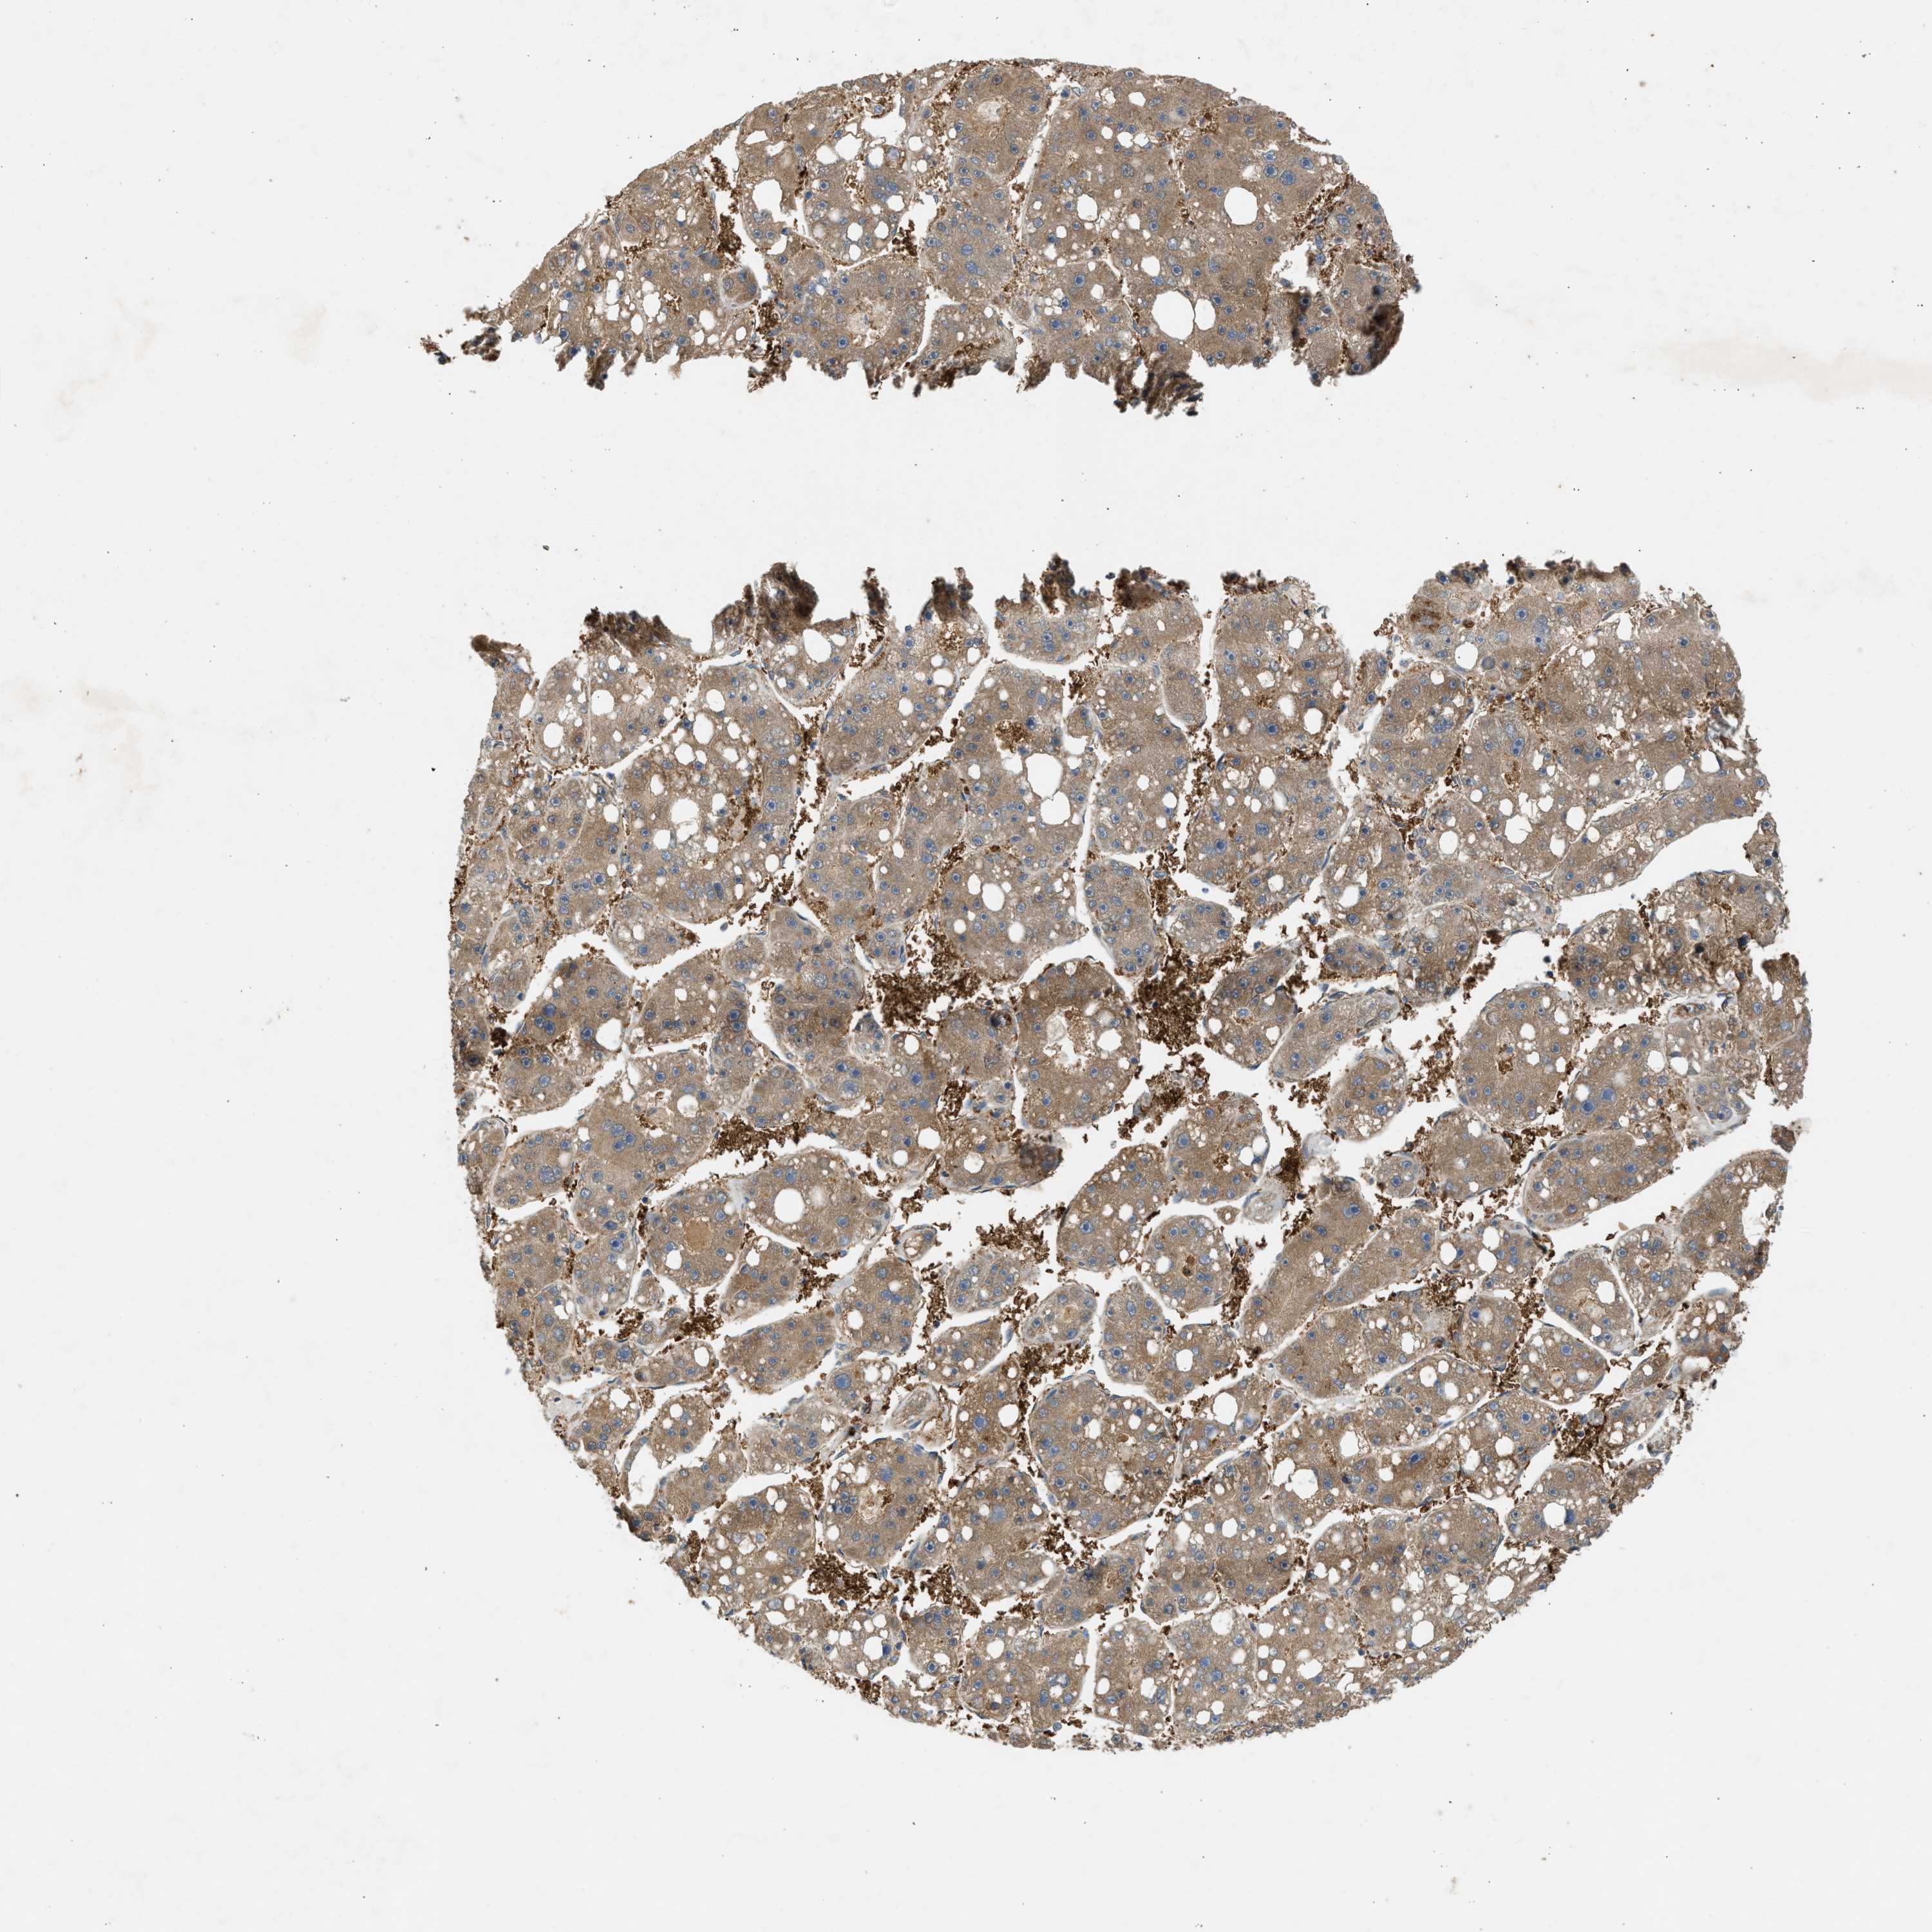

LIVER CANCER - Protein expressioni

A mouse-over function shows sample information and annotation data. Click on an image to view it in a full screen mode. Samples can be filtered based on level of antibody staining by selecting one or several of the following categories: high, medium, low and not detected. The assay and annotation is described here.

Note that samples used for immunohistochemistry by the Human Protein Atlas do not correspond to samples in the TCGA dataset.

Antibody stainingi

Antibody staining in the annotated cell types in the current human tissue is reported as not detected, low, medium, or high, based on conventional immunohistochemistry profiling in selected tissues. This score is based on the combination of the staining intensity and fraction of stained cells.

Each image is clickable and will lead to virtual microscopy that enables deeper exploration of all samples and also displays staining intensity scores, fraction scores and subcellular localization as well as patient and tissue information for each sample.

Antibody CAB018561

Staining

High

Medium

Low

Not detected

Intensity

Strong

Moderate

Weak

Negative

Quantity

>75%

75%-25%

<25%

None

Location

Nuclear

Cytoplasmic/membranous

Cytoplasmic/membranous,nuclear

Cholangiocarcinoma

Carcinoma, Hepatocellular, NOS